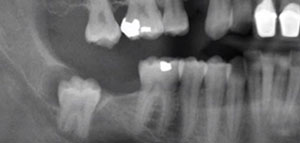

إن عدد الأضراس التي تظهر للإنسان الطبيعي هي أربعة اثنين بالفك السفلي واثنين بالفك العلوي وتظهر بأوقات مختلفة ضمن المرحلة العمرية الطبيعية التي تبدأ بها نمو الاضراس ولكن هناك بعض الحالات النادرة لنموها عند بعض الأشخاص وهي ظهورها كاملة بوقت قصير خلال سنة واحدة وبدون أي ألم وأعراض ومنهم من تتأخر لسن 35 تقريبا يعتبر ألم الأضراس من الآلام الشديدة التي لا يستطيع الغنسان تحملها وتعود أسباب هذه الآلام لعم بزوغها بشكل صحيح بالفك حيث إنه يطهر جزء منها أعلى اللثة والجزء الأكبر يبقى تحت عظام الفك وبهذه الحالة يحتاج لوقت طويل ليخرج ويبقى يسبب الوخز والألم من وقت لأخر

- عدم ظهور البرعم النامي منذ البداية وبقائه تحت عظمة الفك

- نمو ضرس العقل بشكل مائل أو غير عشوائي مما يسبب الكثير من الألم

يظهر ضرس العقل كباقي الأضراس بالفك سليمة وصحية ولكن بسبب ضيق الفك أثناء ظهورها تجعلها عرضة للتسوس والتلف حيث لأنها يمكن أن تنمكو بشكل مائل يؤثر على السن المجاور مما يؤدي بهذه الحالة للتخلص من الضرسين بسبب الألم الشديد الذي تسببه هذه الحالة غير أن جميع الأشخاص يلجؤون لخلع ضرس العقل بسبب تسوسه الكبير لعدم القدرة على ادخال الفرشاة لأخر الفك مما يؤدي لتجمع بقايا الطعام وهي البيئة المناسبة لنمو البكتيريا التي تسبب العديد من الاتهابات بالفم وتسوس الأضراس يتم خلع أضراس العقل بشكل طبيعي عند طبيب الأسنان بحالة ظهور نسبة كبيرة منه أما بحالة عدم ظهوره وبقائه ناميا تحت اللثة فيتم إجراء جراحة لخلعه عن طريق عمل شق صغير من ثم خلع الضرس ويتم المعالجة بعد ذلك بتناول المسكنات وتناول المثلجات لوقف النزيف وبعض المضادات الحيوية